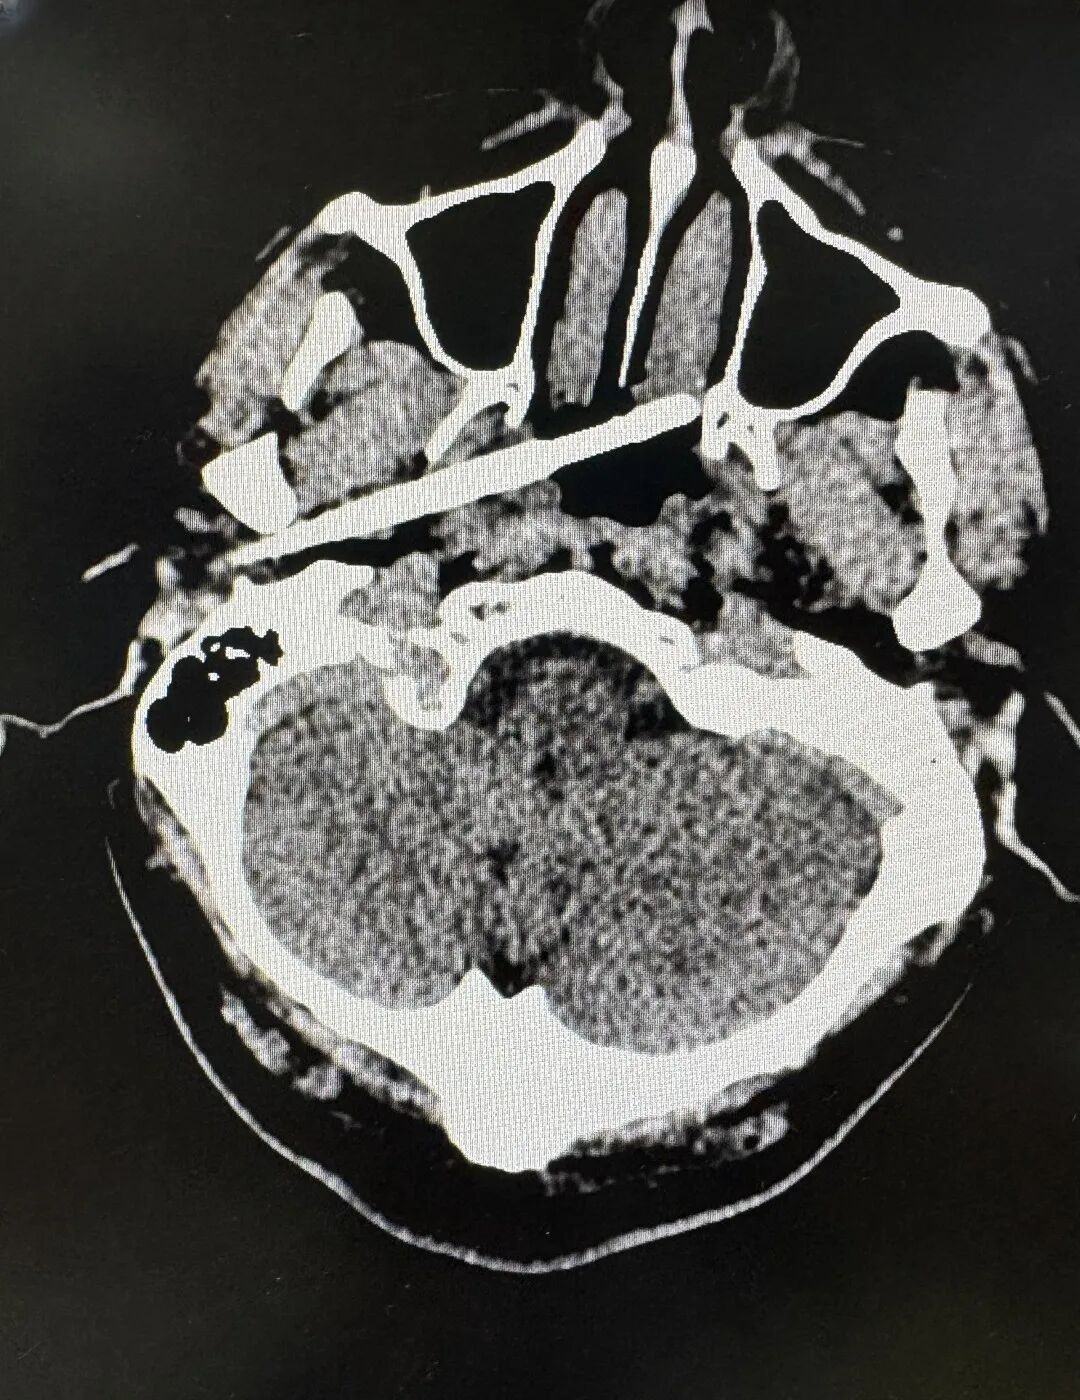

接诊后,创伤中心迅速启动严重创伤救治 “绿色通道”,召集耳鼻咽喉头颈外科、神经外科、影像诊断科、麻醉科专家进行多学科会诊(MDT),通过 CT 血管成像精准定位筷子位置及与血管的关系。

筷子入头影像